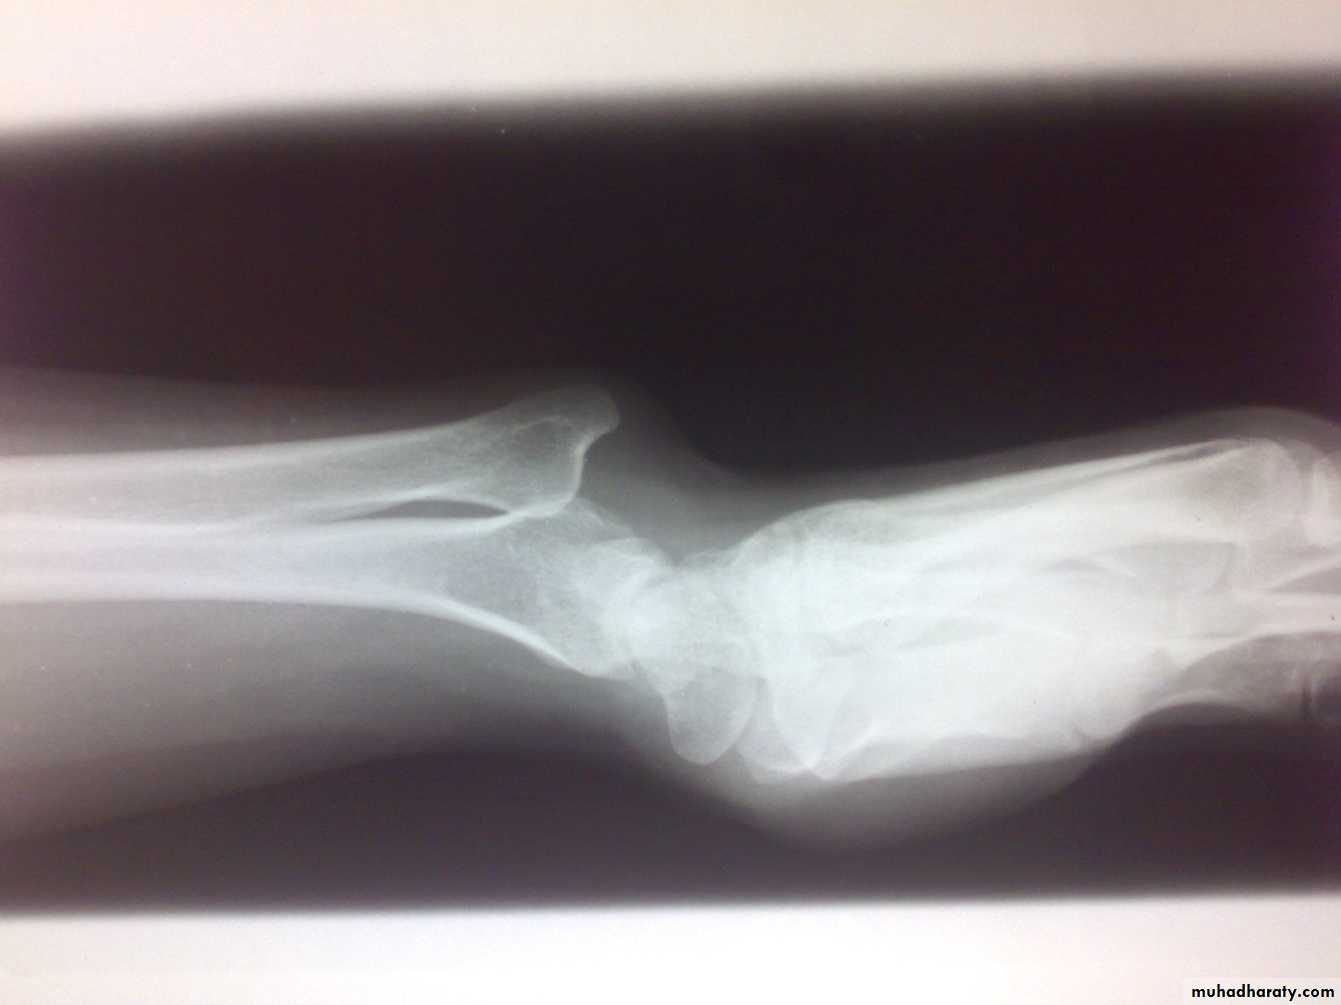

Instability of distal radioulnar joint

Post-traumatic; after fracture of lower radius (Galeazzi fracture dislocation).

Associated with rheumatoid arthritis.

Painful restriction of pronation and supination.

Backward prominence of the lower ulna.

Piano key sign; balloting the lower ulna.